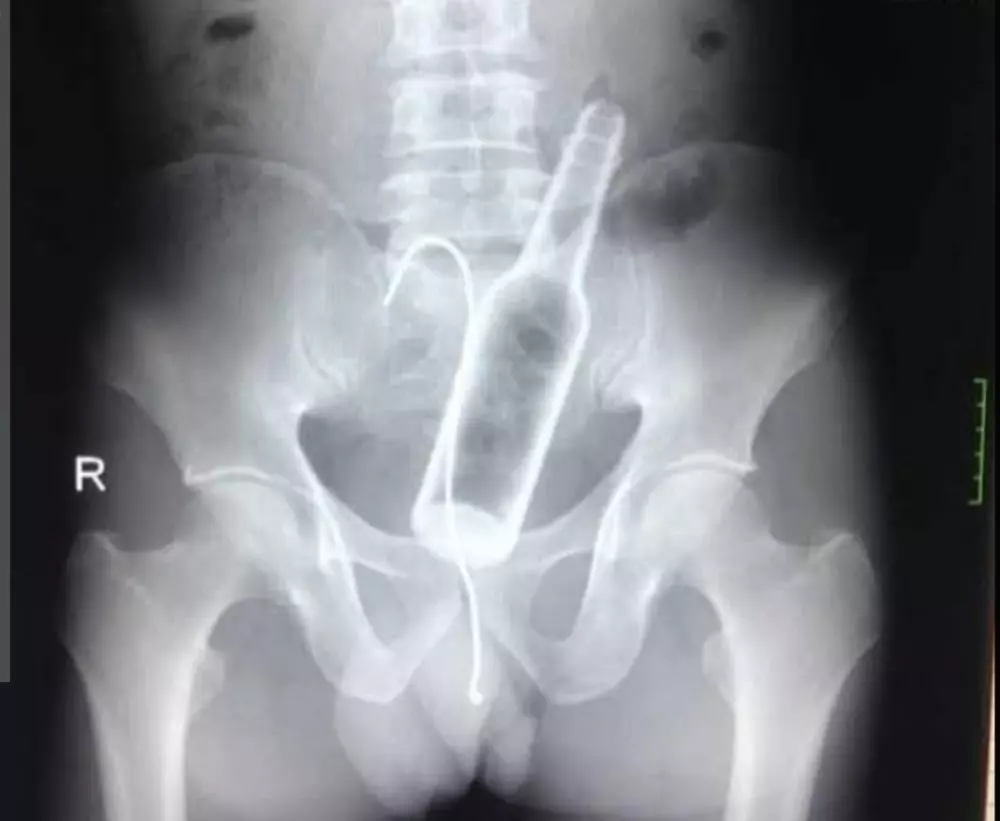

قراءة تقارير التحاليل والأشعه وتقديم ملخص ووصف استشاري عام دون تشخيص أو وصفه علاجيه وتوجيهك لزيارة الطبيب المختص ثمن قراءة تقرير التحليل 10 دولار لكل تقريرين والأشعه كذلك وإن كان هناك استشارات أو أسئله فسيكون ثمن ال5 أسئله 10 دولار ونؤكد على أن المعلومات المقدمه لا تغني عن زيارة الطبيب ولا تعتبر تشخيص نهائي ولا أصف لك دواء فقط اطمئنك على حالتك عوفيتم